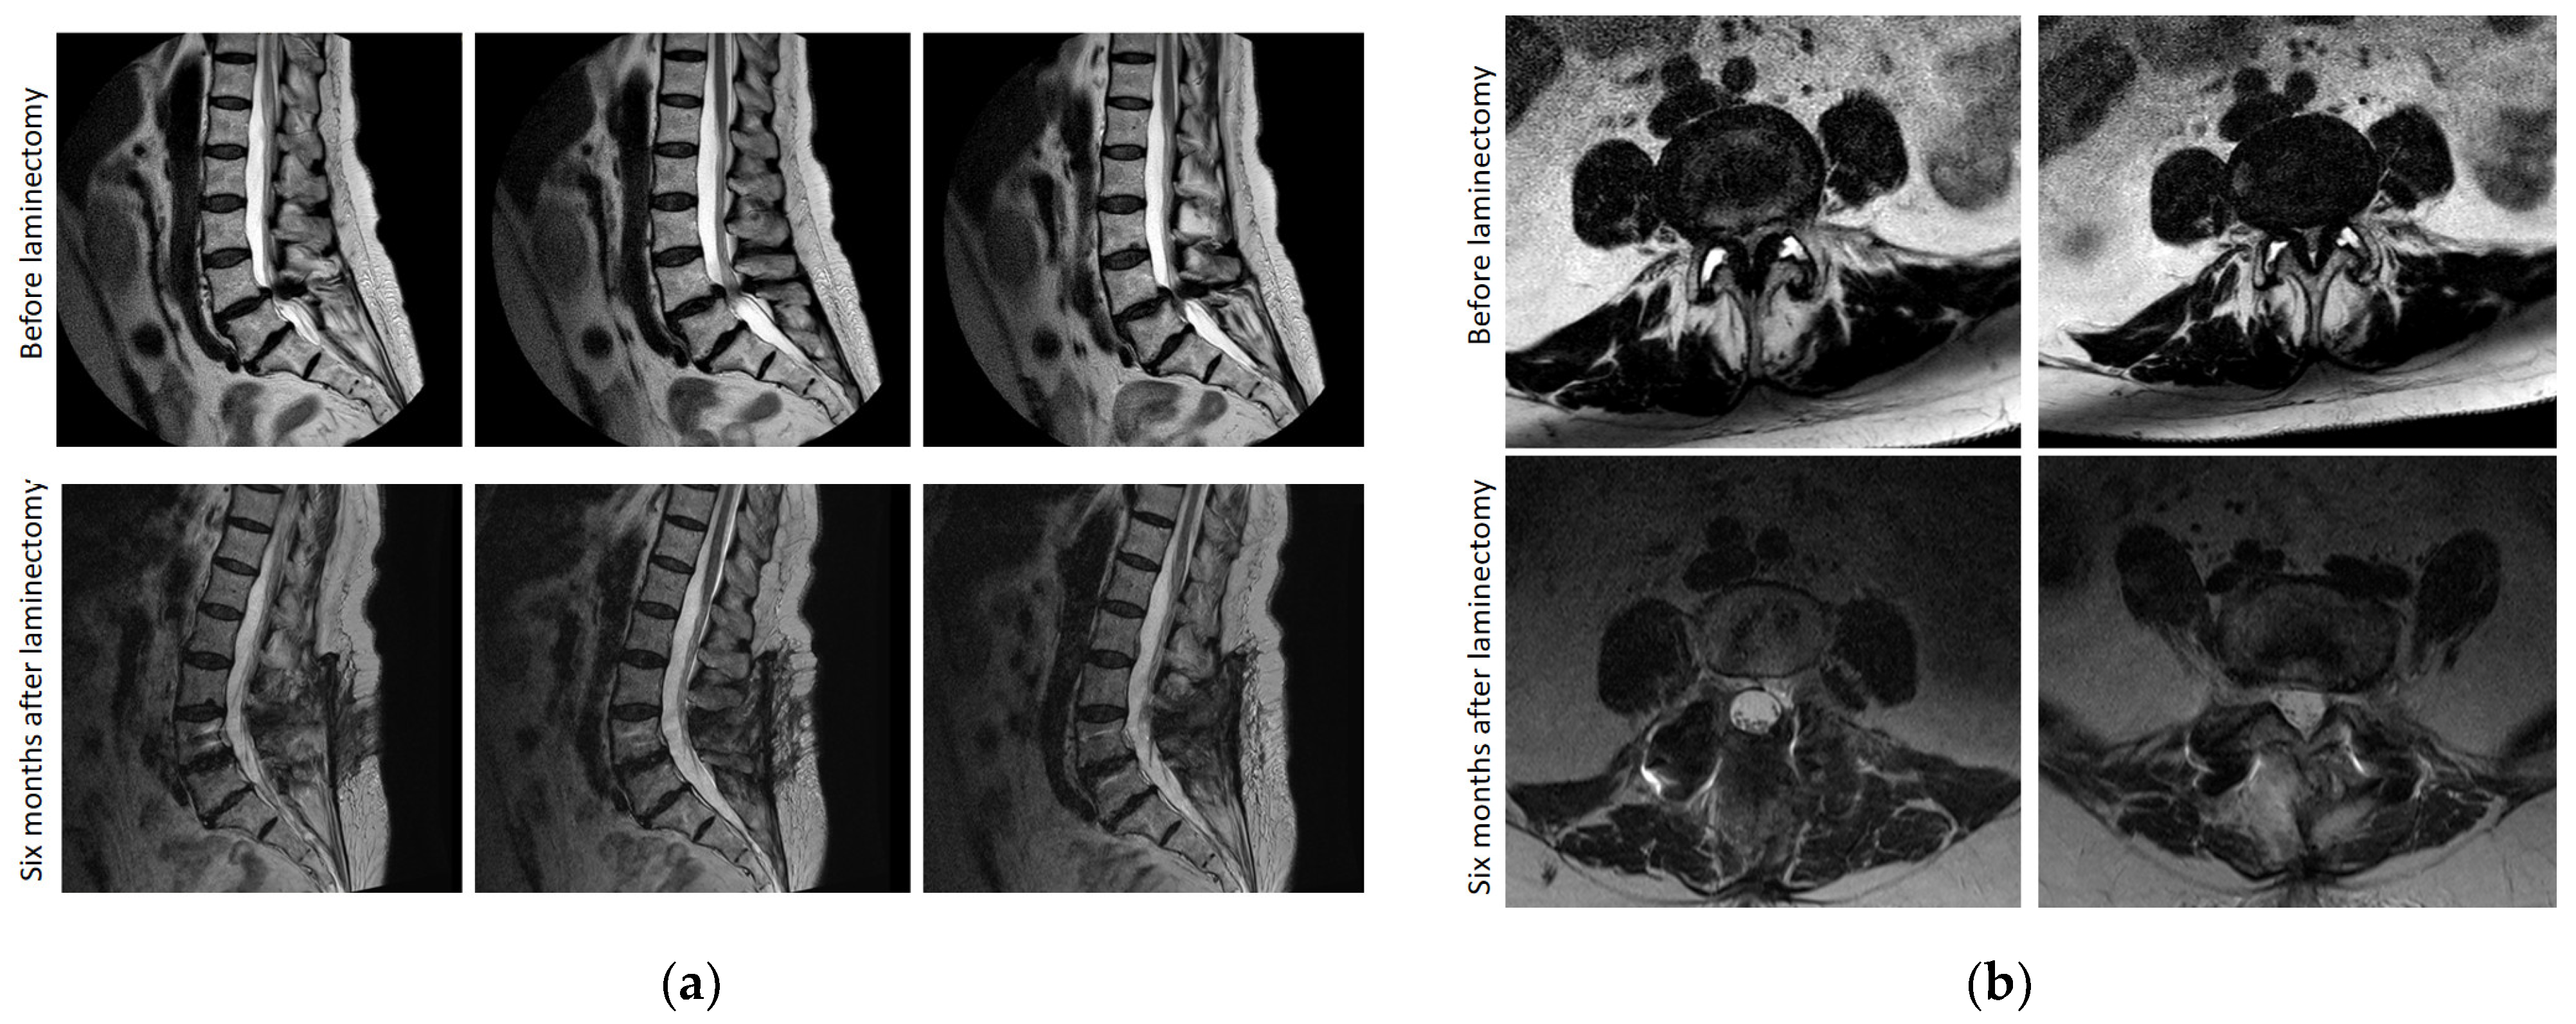

2.3.8. Magnetic Resonance Imaging Founds

3.8. Magnetic Resonance Imaging Examination